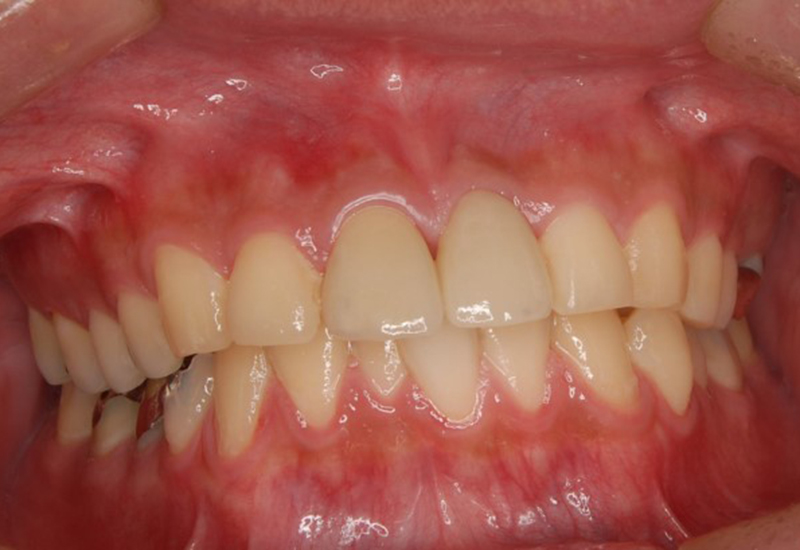

治療前後の写真

治療前 |

治療前